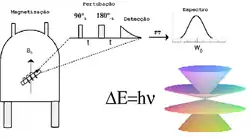

Construção e física

Para realizar um estudo, a pessoa fica posicionada dentro de um scanner de MRI que forma um forte campo magnético em torno da área a ser imageada. Na maioria das aplicações médicas, os prótons (núcleos de hidrogênio) em tecidos contendo moléculas de água criam um sinal que é processado para formar uma imagem do corpo. Primeiro, a energia de um campo magnético oscilante temporariamente é aplicada ao paciente na frequência de ressonância apropriada. Os átomos de hidrogênio excitados emitem um sinal de radiofrequência, que é medido por uma bobina receptora. O sinal de rádio pode ser feito para codificar informações de posição, variando o campo magnético principal usando bobinas de gradiente. À medida que estas bobinas são rapidamente ligadas e desligadas, elas criam o ruído repetitivo característico de uma varredura de ressonância magnética. O contraste entre diferentes tecidos é determinado pela taxa em que os átomos excitados retornam ao estado de equilíbrio. Os agentes de contraste exógenos podem ser administrados por via intravenosa, oral ou intra-articular.[8]

A ressonância magnética nuclear como todas as formas de espectroscopia, trata-se da interação da radiação eletromagnética com a matéria.[6] Entretanto, RMN diferencia-se da espectroscopia óptica em vários aspectos fundamentais, tais como:

primeiro, a separação entre os níveis de energia é um resultado da interação do momento magnético de um núcleo atômico com um campo magnético aplicado; segundo, a interação é com a componente magnética da radiação eletromagnética em vez da componente elétrica.

Sendo que o efeito de RMN ocorre para núcleos que possuem momentos magnéticos e angulares e , respectivamente.

Os núcleos apresentam momentos magnéticos e angulares paralelos entre si, respeitando a expressão onde o fator giromagnético.

Na espectroscopia de RMN é possível controlar a radiação eletromagnética (faixa de radiofrequência ou RF) e descrever a interação desta radiação com os spins nucleares do sistema. Isto contribui em grande parte para o desenvolvimento do grande número de técnicas utilizadas em RMN. Quase todos os elementos químicos têm ao menos um isótopo com um núcleo atômico que possui momento magnético, e quando este é colocado em um campo magnético externo, e a ele for aplicada uma excitação com frequência igual a sua frequência de precessão , tal núcleo é retirado de seu estado de equilíbrio. Após a retirada do campo de RF, este núcleo tende a voltar ao seu estado fundamental de equilíbrio através dos processos de relaxação spin-rede (T1) e relaxação spin-spin (T2)

Em espectroscopia, o processo de ressonância magnética é similar aos demais. Pois também ocorre a absorção ressonante de energia eletromagnética, ocasionada pela transição entre níveis de energia rotacionais dos núcleos atômicos, níveis estes desdobrados em função do campo magnético através do efeito Zeeman anômalo.

O efeito da ressonância magnética nuclear fundamenta-se basicamente na absorção ressonante de energia eletromagnética na faixa de frequências das ondas de rádio. Mais especificamente nas faixas de VHF.